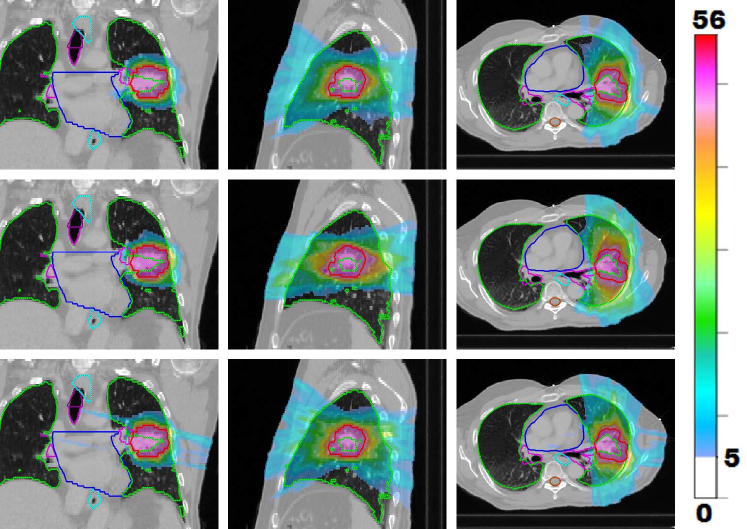

Figure 1: LABEL:sub@prt_allFracs and LABEL:sub@lng_allFracs Fraction-variant treatment plans for each of five fractions for cases “PRT” and “LNG”. The PTV receives a uniform dose of 888 Gy (approximately) at each fraction for case “PRT” and 9.6 Gy (approximately) for case “LNG”. LABEL:sub@hnk_allFracs Dose colormaps for fractions 1, 7, 13, 19, and 25 for case “H&N”. The PTV receives a uniform dose of 2.2 Gy (approximately) throughout the treatment course.

Figure 1LABEL:sub@hnk_allFracs shows the dose distributions for a selection of five of the 30 treatment fractions for the FV head and neck plan. Despite the variation in dose distributions, the PTV is covered uniformly at each fraction. Each voxel in the PTV receives a dose of approximately 66/30=2.266302.266/30=2.2 Gy per fraction. The FV BOO algorithm selected only 6.366.366.36 beams per fraction, on average. As in all cases, the algorithm did not select the same set of beam angles for any two fractions. A total of 81 distinct beam firing positions were utilized, as illustrated in figure 8LABEL:sub@hnk_beams_allFracs.

Figure 9 shows the total dose distribution, summed over all 303030 fractions, for the FV plan (top row) as well as a 7-beam FI plan (middle row) and a 13-beam FI plan (bottom row). Corresponding dose-volume histograms are shown in figure 10. Compared with the 7-beam FI plan, the FV plan achieves dosimetric improvements for the cochleas (bilateral), chiasm, brainstem, parotids, and orbits. Mean dose was reduced by 10.2 Gy (cochleas), 3.4 Gy (chiasm), 1.2 Gy (brainstem), and 1.0 Gy (orbits). Max dose was reduced by 10.0 Gy (cochleas), 6.7 Gy (orbits), 5.7 Gy (brainstem), 4.7 Gy (parotids), 1.6 Gy (brain), and 1.4 Gy (pharynx). The dosimetric quality of the FV plan is comparable to that of the 13-beam FI plan.

Figure 9: Visualizing the dose distribution (summed over all 30 fractions) for FV plan with average of 6.36 beams per fraction (top row) as well as a 7-beam FI plan (middle row) and a 13-beam FI plan (bottom row). Dose below 5 Gy is not shown.